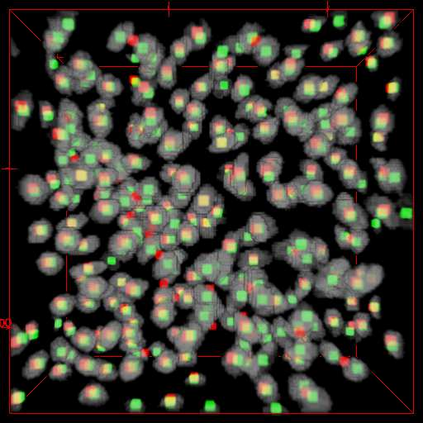

Robust and accurate nuclei centroid detection is important for the understanding of biological structures in fluorescence microscopy images. Existing automated nuclei localization methods face three main challenges: (1) Most of object detection methods work only on 2D images and are difficult to extend to 3D volumes; (2) Segmentation-based models can be used on 3D volumes but it is computational expensive for large microscopy volumes and they have difficulty distinguishing different instances of objects; (3) Hand annotated ground truth is limited for 3D microscopy volumes. To address these issues, we present a scalable approach for nuclei centroid detection of 3D microscopy volumes. We describe the RCNN-SliceNet to detect 2D nuclei centroids for each slice of the volume from different directions and 3D agglomerative hierarchical clustering (AHC) is used to estimate the 3D centroids of nuclei in a volume. The model was trained with the synthetic microscopy data generated using Spatially Constrained Cycle-Consistent Adversarial Networks (SpCycleGAN) and tested on different types of real 3D microscopy data. Extensive experimental results demonstrate that our proposed method can accurately count and detect the nuclei centroids in a 3D microscopy volume.